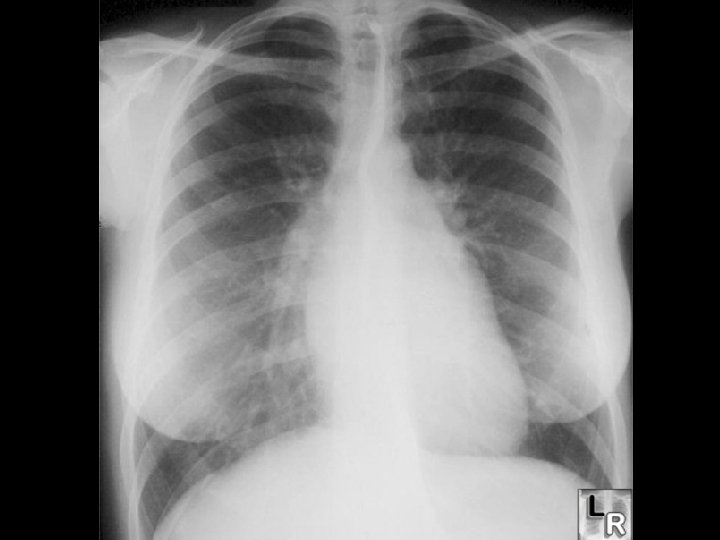

ACUTE RHEUMATIC FEVER (ARF) * Radiographic diagnosis • CXR for cardiomegaly * Laboratory diagnosis • Anti-streptolysin-O (ASO) • Reference ranges • 0 to 3 years • 4 to 17 years • Anti-DNase. B • CRP < 250 IL/m. L <400 IL/m. L